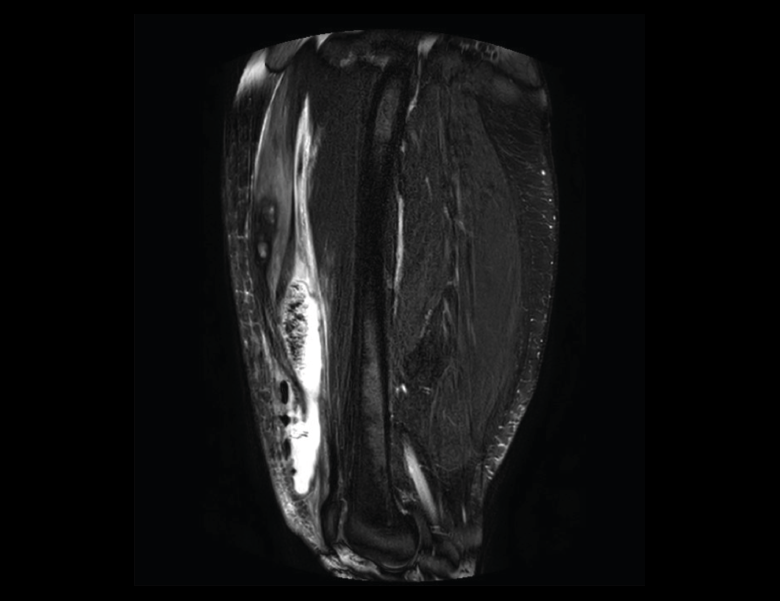

En la osteocondritis se aprecia una lesión subcondral caracterizada por resorción ósea, colapso y la formación de un secuestro.

El estudio por RM es una herramienta valiosa para diagnosticar e identificar las lesiones del cartílago. Conocer el aspecto del cartílago y saber cuánto y cuándo se lesiona, basándose en las clasificaciones actuales, permiten al radiólogo proporcionar la máxima información al clínico(20).

Figura 53. Corte de secuencia sagital (A) y axial (B) T2 Fat-Sat de RM de rodilla: lesiones osteocondrales en el fémur y la rótula.

Numerosos estudios demuestran la utilidad de la RM para definir la estabilidad o inestabilidad de la lesión en la osteocondritis, destacando su carácter no invasivo y la capacidad de valorar la progresión y la respuesta al tratamiento(21)(Figuras 53 y 54).

Figura 54. Corte de secuencia T1 y T2 Fat-Sat coronal de resonancia magnética: gran osteocondritis en el cóndilo femoral interno con edema en la medular adyacente.